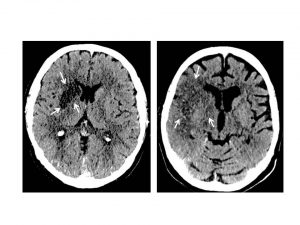

Mehr erfahren zu: "Neue Behandlungsmöglichkeit für viele Schlaganfallpatienten" Weiterlesen nach Anmeldung Neue Behandlungsmöglichkeit für viele Schlaganfallpatienten Eine von Wissenschaftlern des Universitätsklinikums Hamburg-Eppendorf (UKE) geleitete Studie („WAKE-UP“) hat erstmals gezeigt, dass auch Patienten, die im Schlaf einen Schlaganfall erleiden und die Symptome erst nach dem Aufwachen am […]